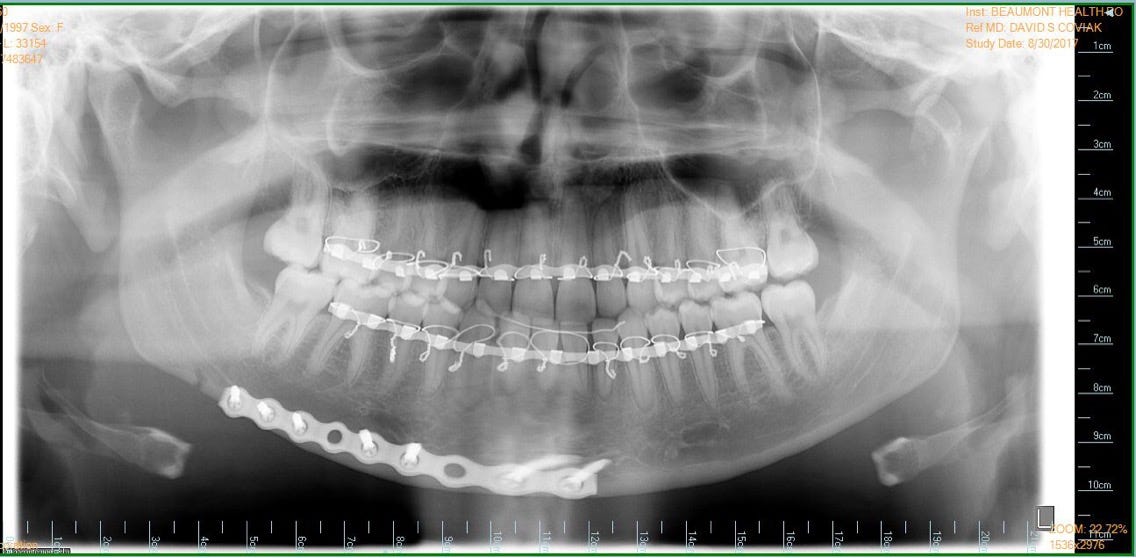

When dentists need to realign your jaw or perform corrective surgery, they may have to break your jaw bones. This procedure is known as orthognathic surgery, and it is performed under general anesthesia to ensure your comfort and minimize pain during the process.

During the surgery, your dentist will carefully make incisions in your gums to access the jawbone. They will then use specialized tools to cut through the bone in a controlled manner, allowing them to reposition it as needed. Once the jaw is in the desired position, your dentist will secure it using small metal plates, screws, or wires to promote proper healing.

Orthognathic surgery, which involves breaking the jaw, is a procedure performed by dentists or oral and maxillofacial surgeons to correct a variety of conditions. These may include misaligned jaws, severe overbites or underbites, facial asymmetry, obstructive sleep apnea, or difficulty chewing and speaking.

By breaking the jaw, dentists can reposition the bones to achieve proper alignment and improve the overall functionality and aesthetics of the jaw and face. The procedure aims to enhance oral health, alleviate pain, and enhance the patient's quality of life.

Once your teeth are properly aligned, your dentist will determine the best surgical approach based on your specific needs. During the surgery, they will break the jawbone, reposition it, and secure it in place using small plates, screws, or wires. The incisions are then closed, and you are taken to the recovery area.